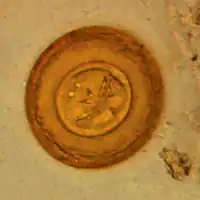

Jaja H. diminuta są okrągłe lub owalne, wielkości 70-86 na 60-80 µm, mają prążkowaną błoną zewnętrzną oraz cienką gładką błoną wewnętrzną. Przestrzeń między tymi błonami jest gładka lub słabo ziarnista. Onkosfera ma sześć haczyków. Jaja H. nana są mniejsze niż H. diminuta, owalne, wielkości 30-55 µm. Na wewnętrznej błonie występują dwa bieguny, z których wychodzą filamenty, biegnące między błonami w liczbie 4 do 8. Onkosfera ma sześć haczyków[2].